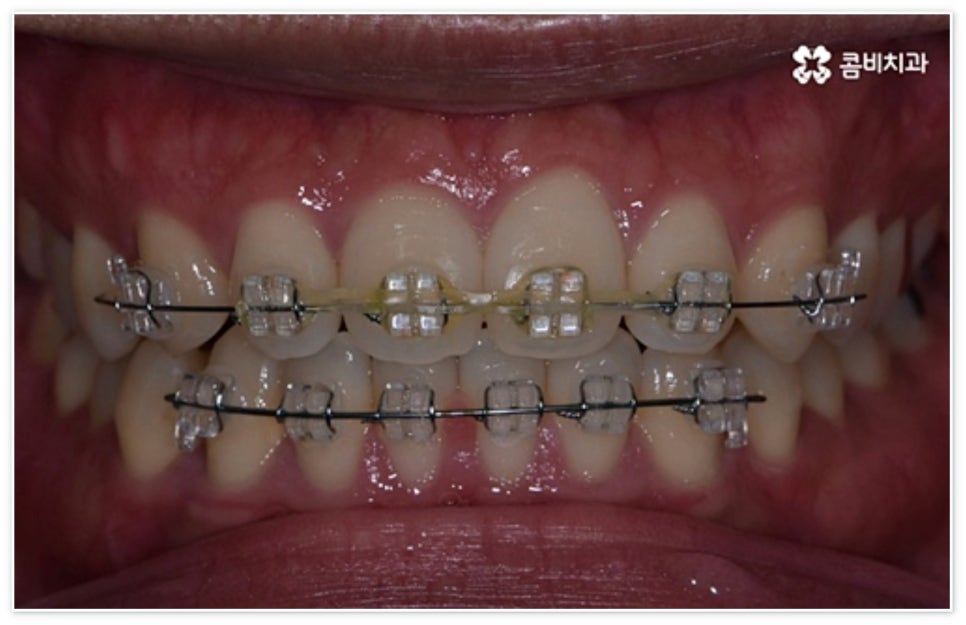

환자분들에 따라 다르지만 통상적으로 전체 교정이 1년에서 2년 반 정도 소요된다면 부분 교정은 6~8개월 정도로 기간 단축이 가능하여 치료에 대한 부담을 줄일 수 있으며 대부분 발치 과정 없이 필요한 부위에만 브라켓을 부착하는 만큼 불편함이 적고 구강 관리도 용이한 편이니 (사진에서 살펴볼 수 있는 케이스) 이에 대해서 자세히 알아보시면 좋을 거예요. 물론 누구나 가능한 것은 아니고 개인의 구강 상태에 따라 진행을 해야 하므로 꼼꼼한 검진과 충분한 상담부터 받아보시길 권유드리고 있습니다.